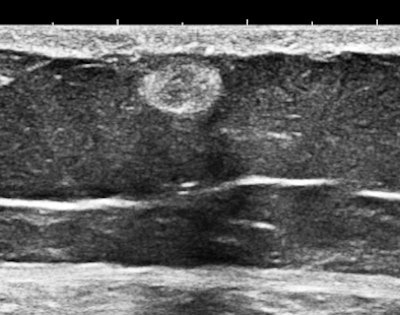

Here are three representative (HD) anterior abdominal wall images at 15 MHz:

Mast cells and mediator-release disorders

These echogenic "nodules" are tumorlike collections and cellular infiltrates of mast cells. The precise diagnosis is systemic mast cell disease. Symptoms are due to mediator release. At one pole is typical carcinoid syndrome involving serotonin and kallekrein, and at the other extreme is anaphylaxis with predominant histaminelike substances. Because of the large number of nodules, there is a significant neuroendocrine burden, similar to the multiple metastases of a malignant carcinoid tumor filling the liver.

Soft, well-demarcated reflective nodules in subcutaneous fat are an Aunt Minnie of a sign. They are not palpable, and I suspect they can only be found by high-frequency ultrasound, which is perfect for outpatient screening applications. There may be a completely unexpected, relatively high prevalence of this finding, and it seems that multiple nodules may predispose several allergic disorders, including conditions such as irritable bowel syndrome (IBS), fibromyalgia, and possibly even exercise-induced asthma or postexertional hypotension and reactive tachycardia.